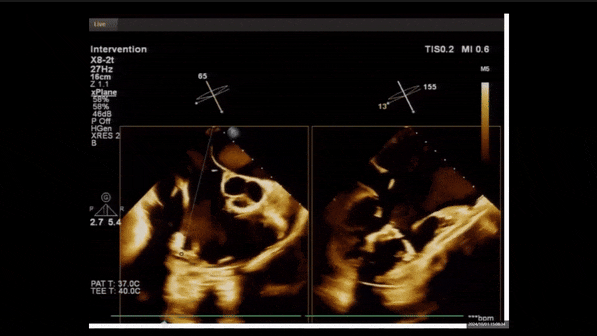

術前TEE評估

1、3D TEE顯示雙房及右室擴大,右室中段直徑40mm,右室FCA 52%。三尖瓣環TAPSE 22mm,三尖瓣環左右徑49mm,三尖瓣隔葉長度16mm,前葉長度21mm,后葉長度34mm,三尖瓣前隔gap 11mm,后隔gap 5.6mm,AP gap 12mm,診斷極重度功能性三尖瓣返流(Type I型三尖瓣:Torrential FTR 5+)。

2、彩色多普勒顯示:收縮期三尖瓣口返流束起源于后隔交界、前后葉之間及前隔交界,返流束縮流頸最大寬度27mm,三尖瓣返流口EOA=2.02cm2,返流容積124ml,收縮期三尖瓣返流峰值速度2.64m/s,返流峰值壓差28mmHg,PAPs 43mmHg,舒張期三尖瓣口平均跨瓣壓差1mmHg,肝左靜脈可見明顯逆向血流波。